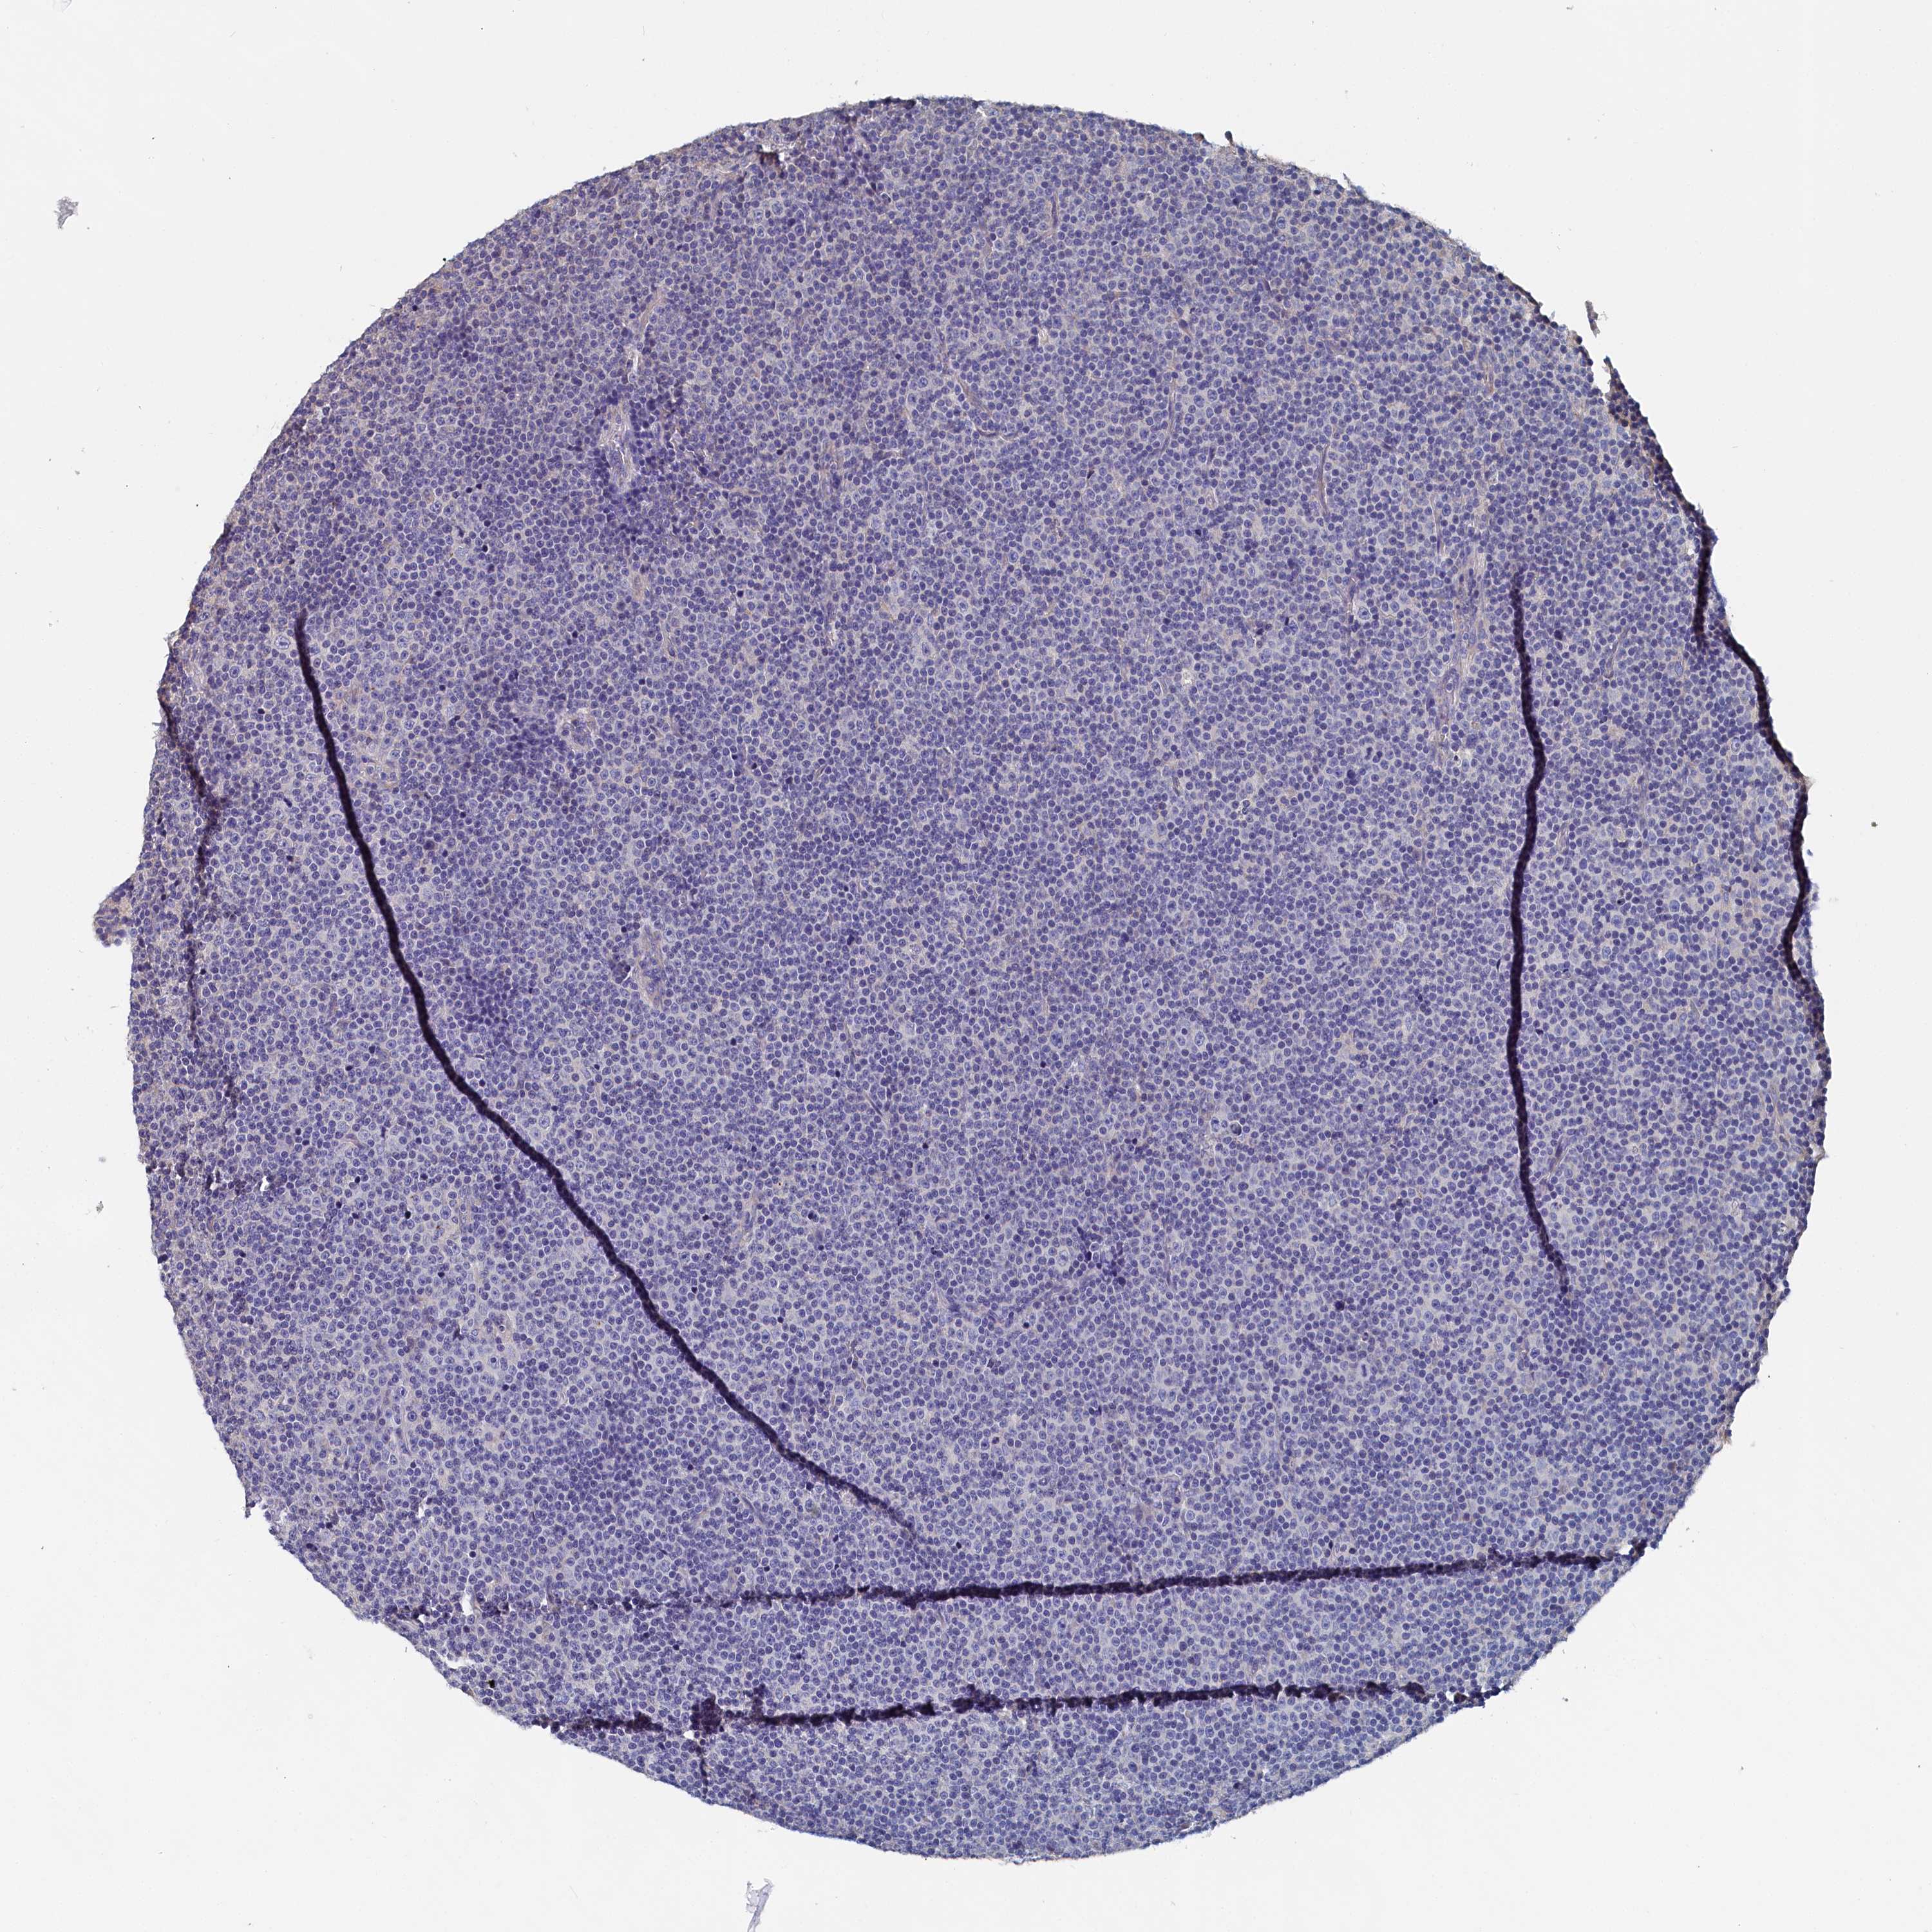

CANCER LYMPHOMA Show tissue menu

LYMPHOMA - Protein expressioni

A mouse-over function shows sample information and annotation data. Click on an image to view it in a full screen mode. Samples can be filtered based on level of antibody staining by selecting one or several of the following categories: high, medium, low and not detected. The assay and annotation is described here.

Each image is clickable and will lead to virtual microscopy that enables deeper exploration of all samples and also displays staining intensity scores, fraction scores and subcellular localization as well as patient and tissue information for each sample.

Antibody HPA038285

Antibody HPA058310

Hodgkin's disease, NOS

Malignant lymphoma, non-Hodgkin's type, High grade

Malignant lymphoma, non-Hodgkin's type, Low grade